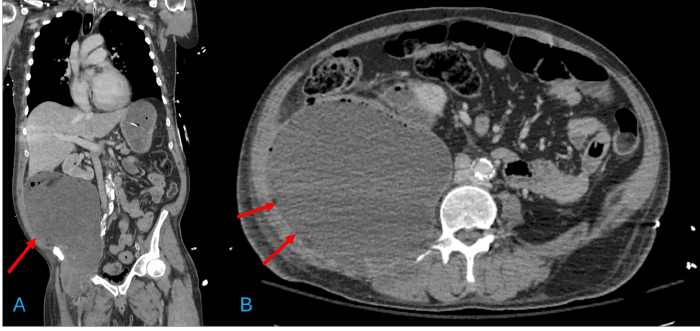

The patient was admitted to the intensive care unit (ICU) with a diagnosis of acute respiratory failure secondary to cardiopulmonary arrest, acute PE, and severe lactic acidosis. Broad-spectrum antibiotics, fluid resuscitation, vasopressor support, and venous thromboembolism prophylaxis were initiated. Interventional radiology (IR) was consulted for percutaneous drainage. Under fluoroscopic guidance, IR successfully accessed the retroperitoneal abscess, draining approximately 2.8 liters of purulent fluid (Figure 2). Further imaging revealed an extensive deep venous thrombosis (DVT) involving the right common femoral vein and extending to the calf veins, as well as the deep femoral and greater saphenous veins. This was presumed to be secondary to mass effect and compression of the femoral vasculature by the large abscess.

Figure 2. Percutaneous Drainage of Retroperitoneal Abscess. Published with Permission

Image obtained during IR placement of a percutaneous drain under fluoroscopic guidance. The catheter is seen being advanced into the large right retroperitoneal fluid collection for initial source control